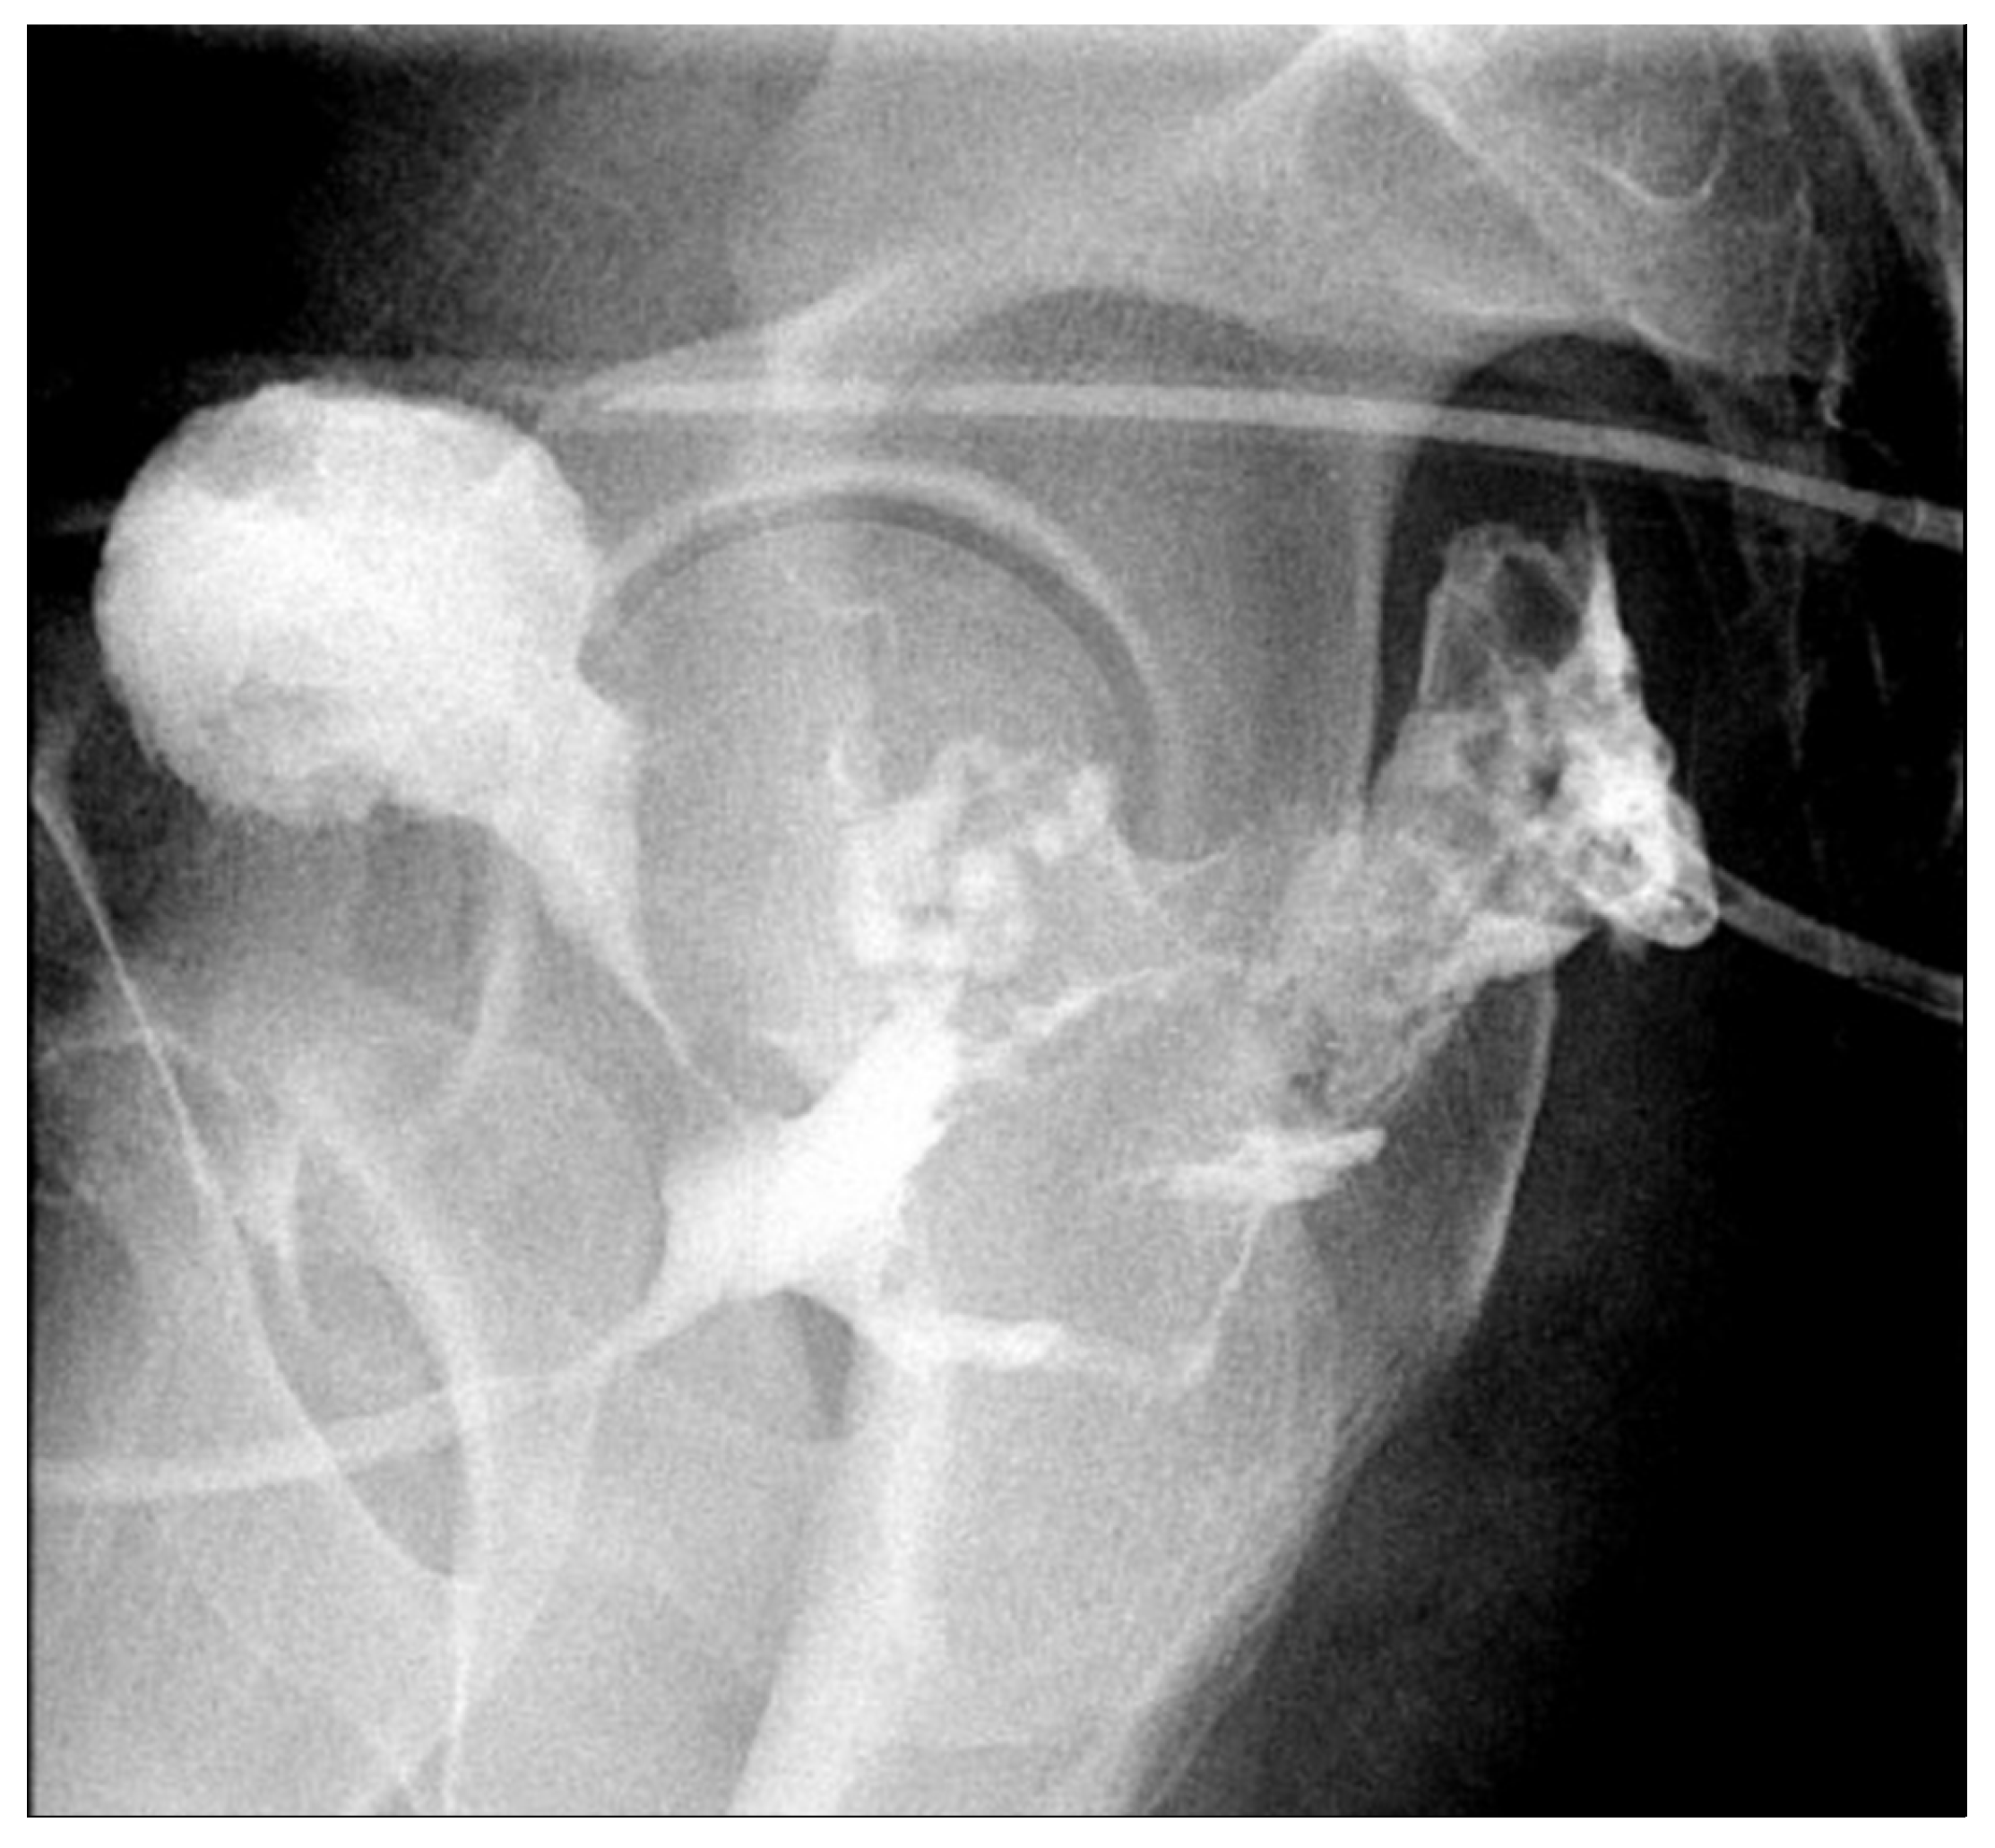

3.1. Case 1

3.2. Case 2